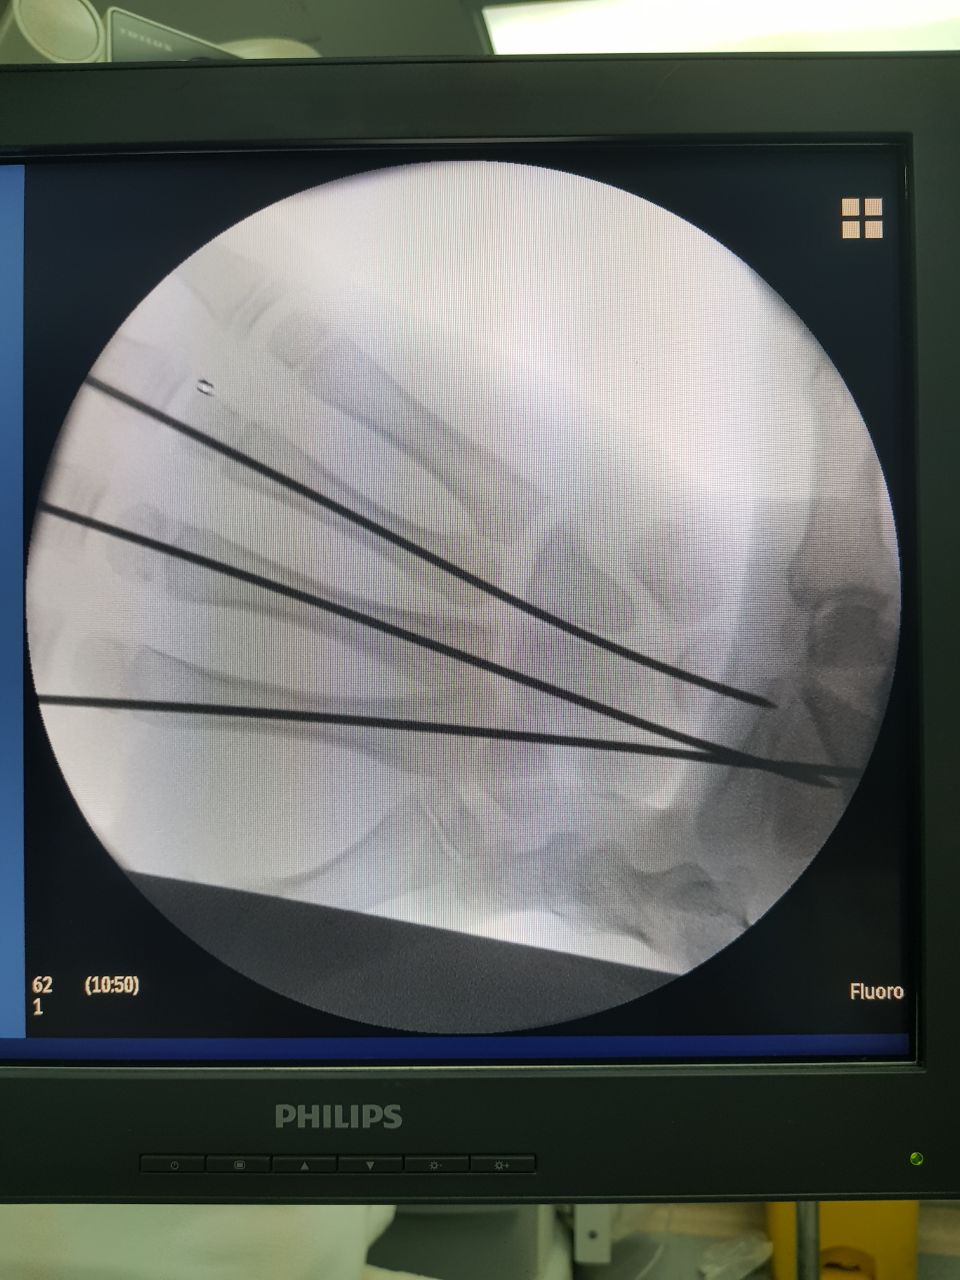

نجح فريق طبي متخصص في مستشفى أبوعريش العام بقيادة طبيب العظام الدكتور محمد الشافعي، والأطباء المساعدين الدكتور أيمن مطاوع، والدكتور ضيفي محمد، وطبيب التخدير الدكتور عباس، في إجراء جراحة عاجلة ونادرة لحالة طفل تعرض لحادث مروري نتج عنه خلع مشطيات اليد اليمنى بشكل كامل.

وتمثلت الجراحة في الرد المغلق وادخال الاسلاك المعدنية (IC.wires) من نهاية المشطيات عن طريق فتحات لا تتجاوز ٢مم وتثبيتها بالرسغ.

وتكمن صعوبة الجراحة في صغر سن الطفل وصغر عظام الطفل والتورم الشديد.